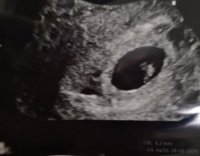

Eka neuvola takana ja sieltä saatiin aika neuvolalääkärille vk 10. Ei tullut kysyttyä, että ultrataanko siellä. Kai? Vai onko nuo ultrat aina erikseen jossain polilla?

Meiltä on tunnin matka lähimpään yksityiseen ultraan, joten kiva näin. Äitiyspolilla nt-ultra sit vasta kunnon tutkimus ja määrittää lopullisen l.a:n.

Hinta oli 128e. Ainoa mikä ihmetytti että kuuluisiko ultralaitteesta kuulua sykkeen ääni? Sykkeen kyllä näin kun minulle näytettiin mistä katsoa, mutta mitään tuosta laittesta ei kuulunut...